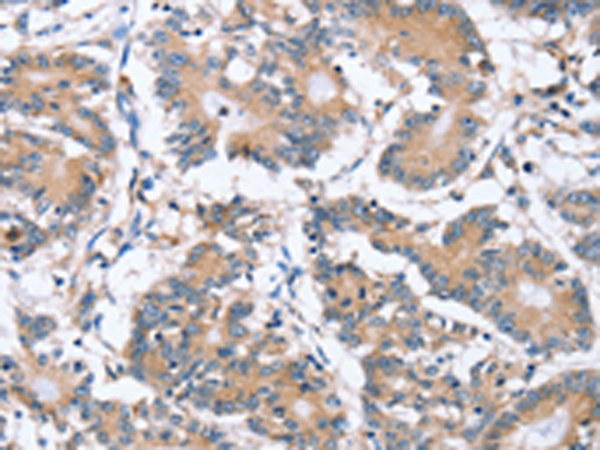

分类: 科研抗体货号: P08628别名: SAK; STK18; MCCRP2应用: IHC反应种属: Human, Mouse, Rat